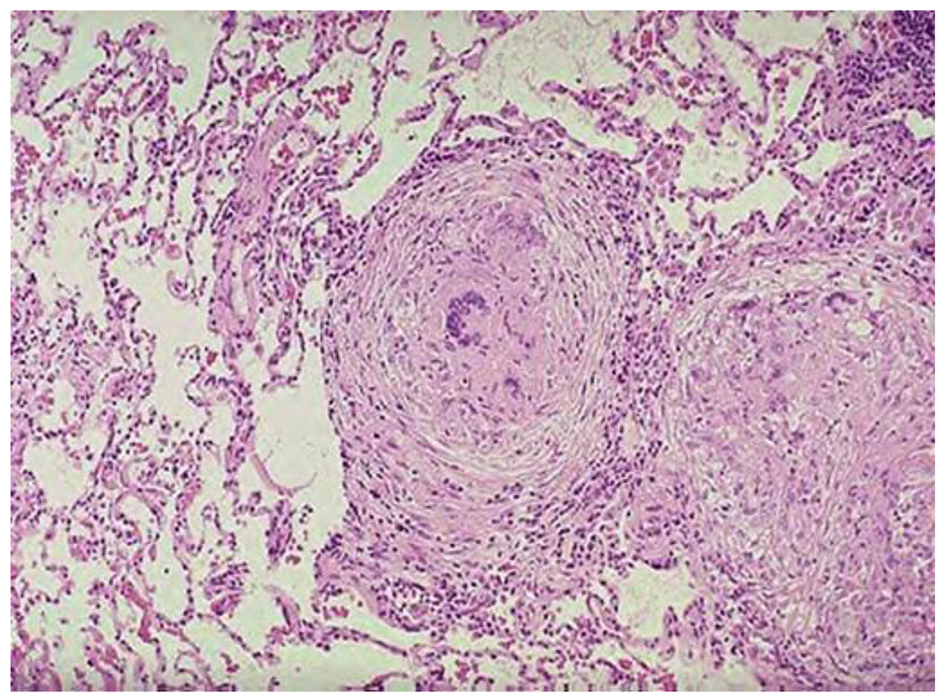

Микроскопический взгляд на мишитарный туберкулез легкого: фотодокументация

Раздел: Снимки-откровения